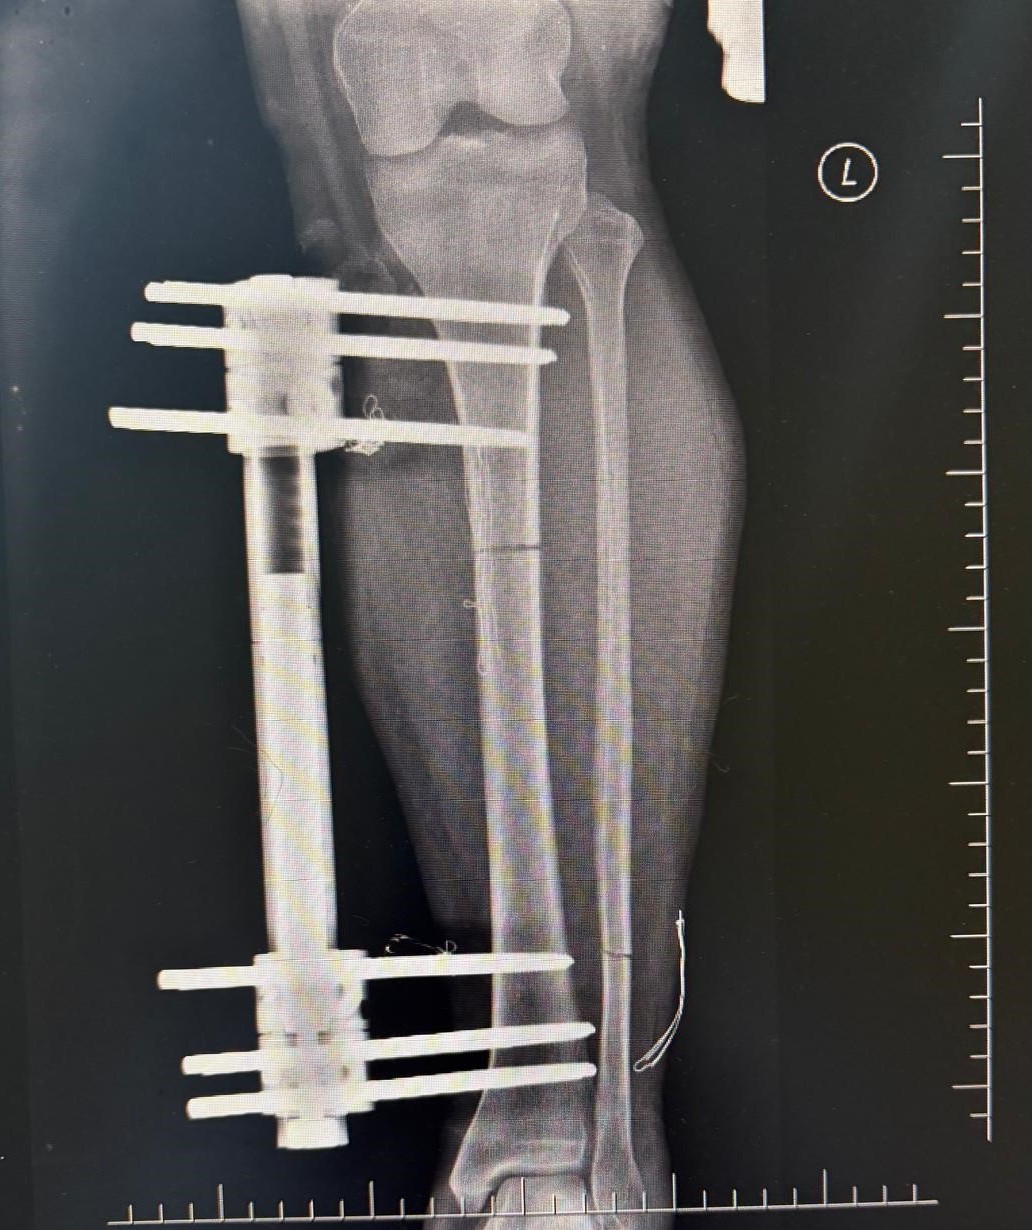

Ameliyat aşamasının ardından gerçekleşen süreci tek tek dile getiren Ortopedi ve Travmatoloji Uzmanı Prof. Dr. Mahmut Argün, "Hastamız 1.58 boyunda olması nedeniyle sürekli boyunun kısalığından dolayı hem fiziksel hem de bedensel rahatsızlıkların olduğunu dile getirdi. Israrla boyunun uzatılmasını bizden talep eden hasta 2 aşamalı olunması gereken muayeneyi 1 aşamalı olmasını istedi. Sol tarafından başlayarak hem femur hem de tibia 5 ila 6 santimetre arasında uzatmayı planladık. Hastamızı ameliyata alıp bu işlemleri gerçekleştirdik. Hasta şuanda uzatma işlemlerinin yapılabilmesi için malzeme yerleştirme aşamasını gerçekleştirdik. Ameliyattan 10 gün sonra uzatma işlemlerini başlayacağız. Uzatma işlemleri yaklaşık 60 gün sürecek. Uzatma işlem süreci geçtikten sonra işlemi durdurup kaynaması için 2-3 ay bekleyeceğiz. Ardından ise hastanın üzerinden malzemeleri yaklaşık 150-200 gün arasında çıkaracağız. Bu tarz işlemler meşakkatli ve özen isteyen ameliyatlar" diye konuştu.

Uzama sürecinde her gün 1 milimetre olmak üzere kurulan mekanizmanın başladığını dile getiren Ortopedi ve Travmatoloji Uzmanı Op. Dr. Necip Özateş, "Her gün 1 milimetre olmak üzere, üzerindeki mekanizma üzerinden hem uyruk kemiği hem kaval kemiği uzatılmaya başlıyor. Hem bu şekilde kemik uzaması hem de bu esnada kemik kaynaması aynı anda olduğu için daha kontrollü bir işlem oluyor. Hedef uzunluğa ulaştığımızda uzatma işlemini sonlandırıyoruz. Sonrasında da kemiğin kaynaması sürecine geçiyoruz" dedi.